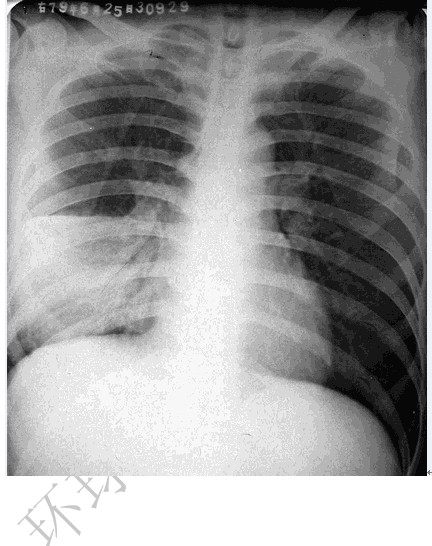

大叶性肺炎

图示为右肺中叶大叶性肺炎

(1)胸部正位